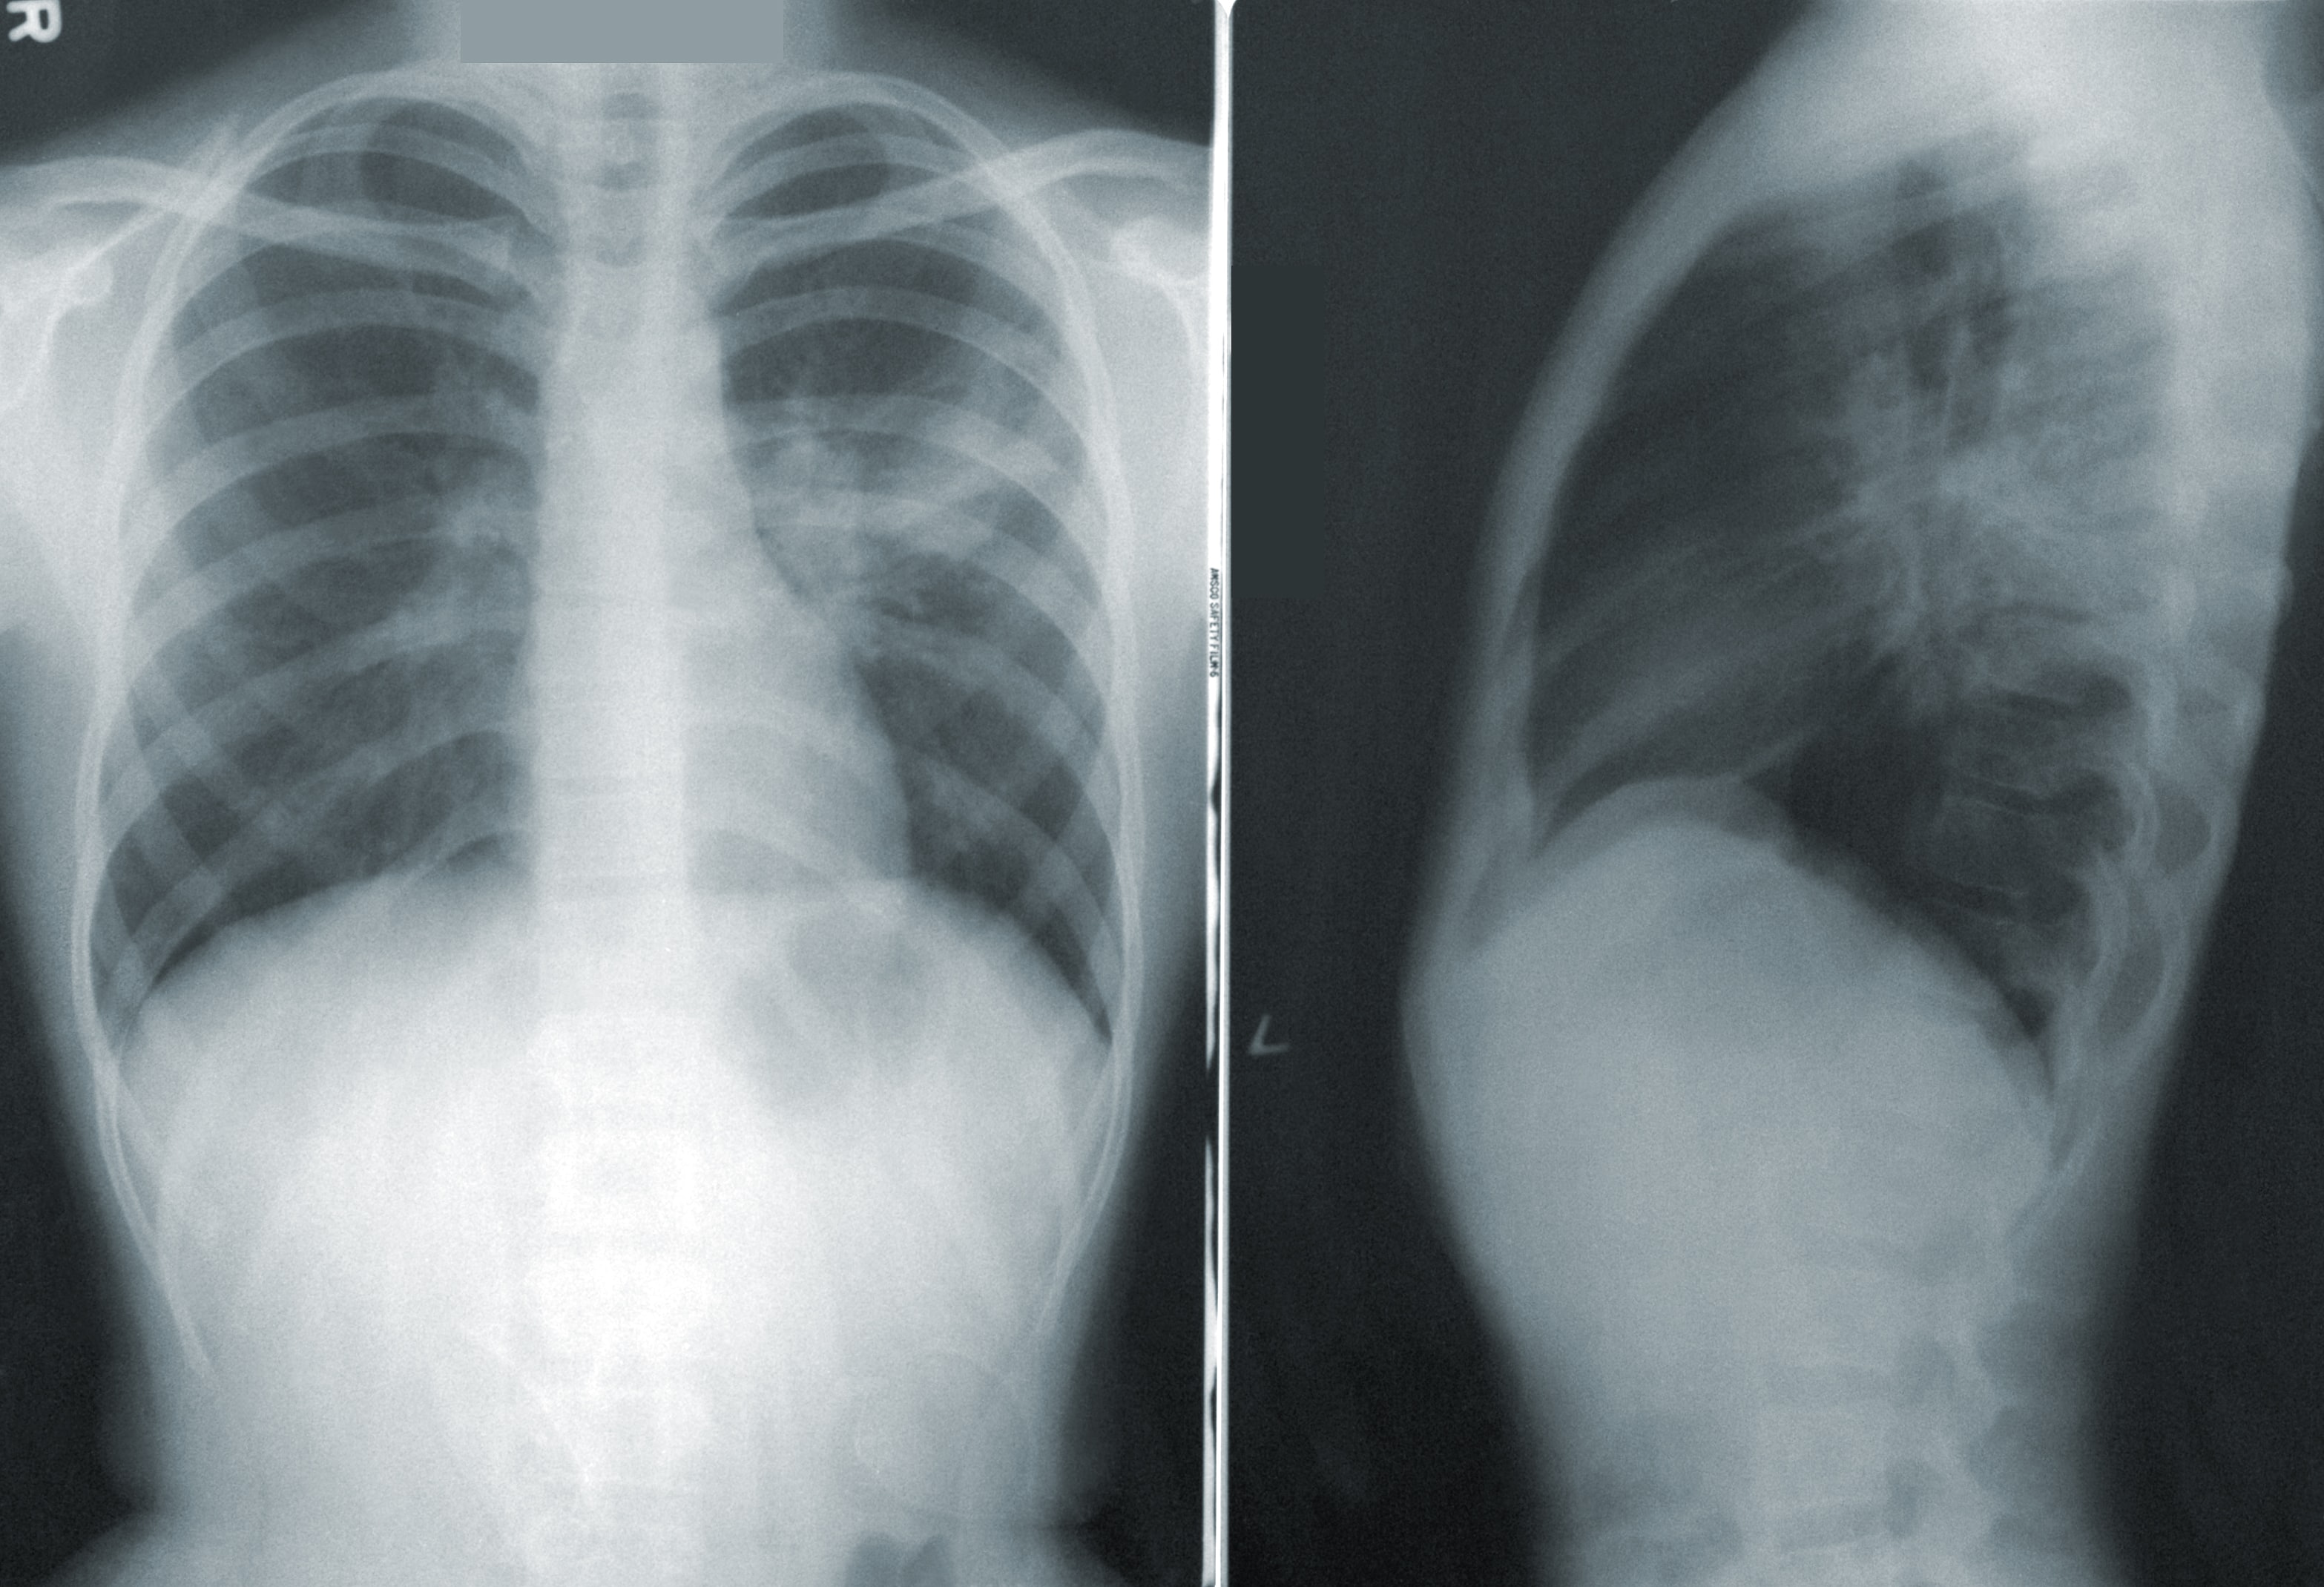

X-Ray showing pneumonia. CDC on Unsplash.

New research using machine learning on images of everyday items is improving the accuracy and speed of detecting respiratory diseases, reducing the need for specialist medical expertise. Edith Cowan University (ECU) researchers trained algorithms on a database of more than 1 million commonplace images and transferred this knowledge to identify characteristics of medical conditions which can be diagnosed with an x-ray.

Edith Cowan University (ECU) researchers trained algorithms on a database of more than 1 million commonplace images and transferred this knowledge to identify characteristics of medical conditions which can be diagnosed with an x-ray.

Results of this technique, known as transfer learning, achieved a 99.24 per cent success rate when detecting COVID-19 in chest x-rays.

“Our technique has the capacity to not only detect COVID-19 in chest x-rays, but also other chest diseases such as pneumonia. We have tested it on 10 different chest diseases, achieving highly accurate results,” he said.